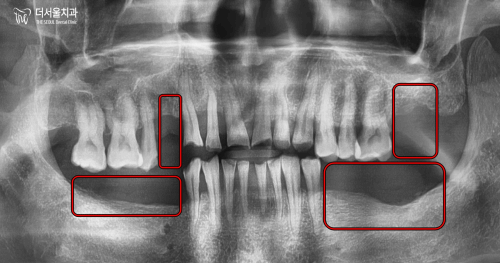

초진 구강 사진을 보면

곳곳에 이가 빠져서 빈 곳이 있고

남아있는 이들이 깨지고

벌어져있습니다.

바로 어금니가 없기 때문입니다.

식사를 할 때 중축이 되는 대구치는

총 8개가 있어야 되는데요.

현재 3개밖에 남지 않았으며

맞물리는 이가 없어서

제 기능을 하지 못하고 있죠.